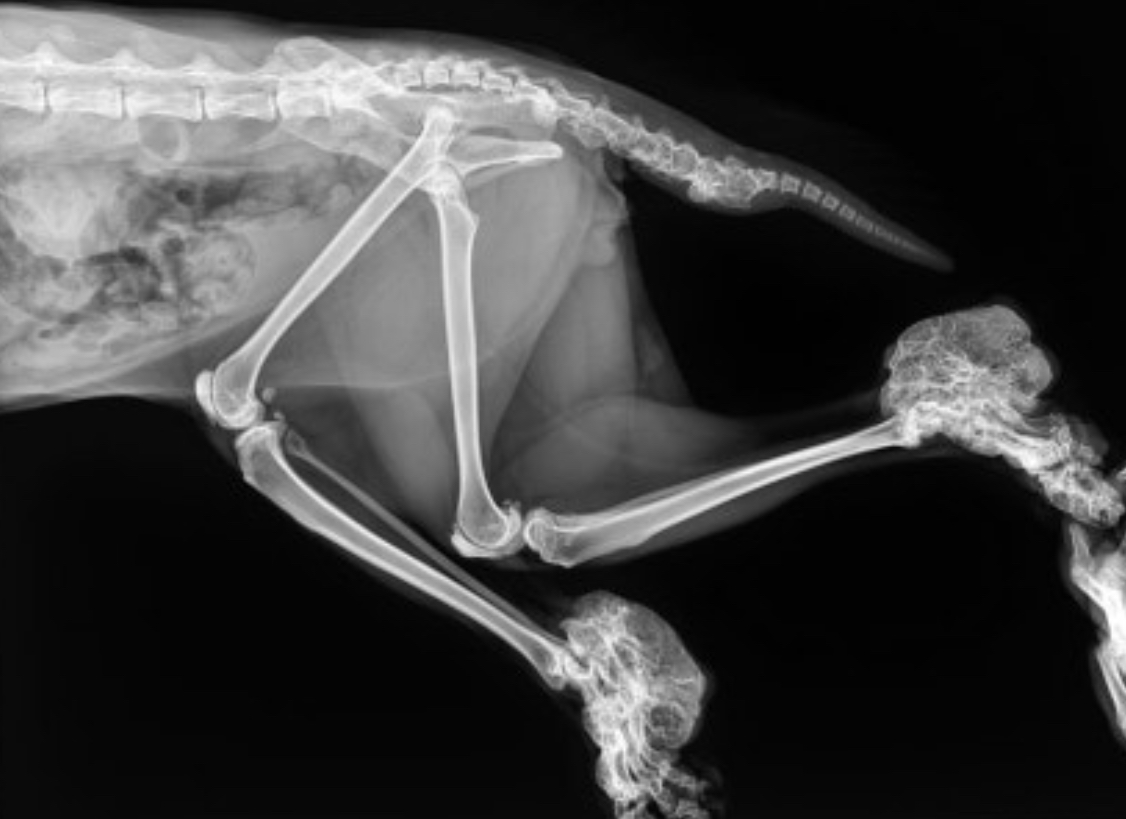

이러한 증상이 나타난 경우, 빠른 진단과 치료가 필요합니다. 가장 기본적인 진단 방법은 X-ray 촬영이며, 뼈와 관절의 이상을 시각적으로 확인할 수 있습니다. 진단 후에는 통증 완화를 위한 약물치료, 물리치료, 경우에 따라 수술이 고려될 수 있습니다.

골연골 이형성증은 스코티쉬 폴드 품종 고양이에게서 나타나는 대표적인 유전 질환입니다. 이 질환은 귀의 연골뿐 아니라 전신의 뼈와 관절에도 영향을 미치며, 특히 꼬리, 발목, 다리 부위에 강직이나 변형이 나타납니다. 초기에 나타나는 증상은 뒷다리의 절뚝거림, 점프를 꺼리는 행동, 낮은 활동성 등으로 시작되며, 점차 관절에 염증과 통증이 심화됩니다.

골연골 이형성증(Osteochondrodysplasia)은 뼈와 연골의 형성이 비정상적으로 이루어지는 유전 질환입니다. 특히 스코티쉬 폴드 고양이는 이 질병을 유발하는 FDFT 유전자 돌연변이를 보유하고 있는 것으로 알려져 있습니다. 이 유전자는 귀의 연골이 접히게 만드는 원인이기도 하지만, 동시에 전신의 연골 형성에 영향을 주기 때문에 관절의 비정상적인 성장과 만성적인 통증을 초래할 수 있습니다.

문제는 이 질병이 단순한 미용적인 이슈가 아니라는 점입니다. 뼈와 관절의 변형은 성장기부터 나타나며, 고양이가 걷기 힘들어하거나 움직일 때 통증을 호소하는 증상이 나타납니다. 일부 고양이들은 후지 마비나 휜 다리, 꼬리의 움직임 제한 등 일상생활에 심각한 불편을 겪습니다. 이런 증상은 시간이 지날수록 악화되며, 결국 평생 관리가 필요한 만성 질환으로 이어집니다.